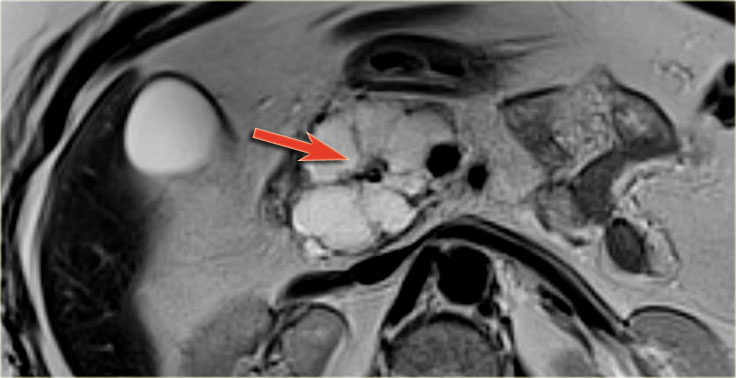

MRI better demonstrates the morphologic features of the lesion (fig).

On T2WI the lesion is multicystic.

Note the central low signal due to the central scar with calcifications.

Although some of the cysts are rather large, this is still a characteristic appearance of a serous cystic adenoma (macrocystic form).